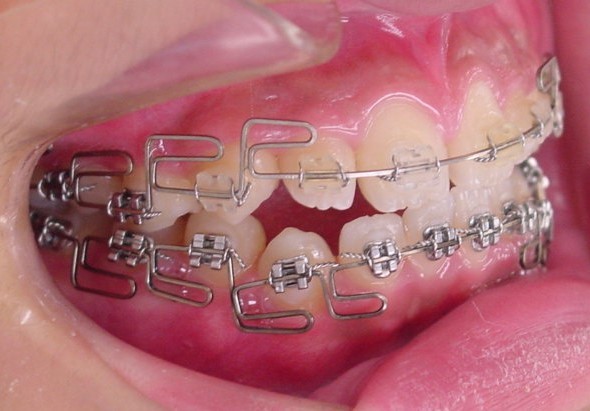

当院では出っ歯(上顎前突)を非抜歯(第一小臼歯を抜歯しない)で治療するために

MEAW(マルチループ)を利用してように治療を進めていきます。

見えにくい矯正装置(ブラケット)で歯列を並べていきます。

歯並びが整ったら矯正装置を取り替えます。

MEAW(マルチループ)で咬み合わせの高さを

改善していきます。